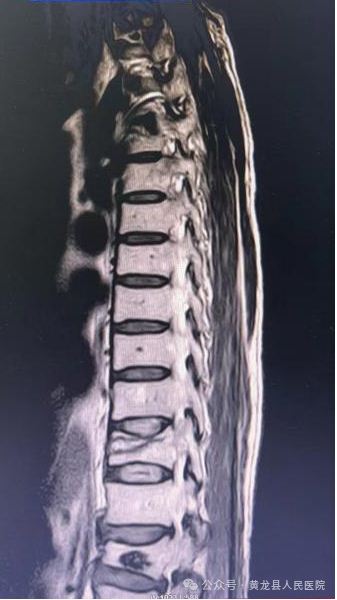

术前MRI 和术后X线影像图片

“经皮椎体成形术”此项手术操作精细,术中切口小,创伤出血少,且无需广泛切开肌肉韧带等软组织,从而避免了肌肉软组织剥离过多所导致的迟发性脊柱不稳。由于手术创伤小,术后患者恢复快,可以早期下床活动,对病人术后的功能锻炼和恢复提供了有利的条件,很大程度减少了病人痛苦。